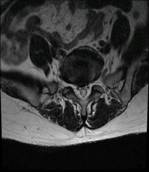

术前MRI检查

患者辗转于西安多家医院,被告知需进行手术治疗,因担心手术较大,出血多,后遗症多,迟迟不能决定手术。经别人推荐慕名找到我院骨科脊柱微创中心的张银刚教授。张银刚教授和刘凯博士等细致了解病情,仔细查体和阅片后分析:该患者腰5-骶1椎间隙退变严重,椎间隙变窄,腰5椎体失稳并向前滑脱,与增生的黄韧带和骨赘组织共同作用,造成腰椎管狭窄。进而引起腰痛、间歇性跛行等症状。

患者,女性,53岁。因患有“腰5椎体滑脱症、腰椎管狭窄症”被腰痛和跛行折磨多年,只能自主行走不到100米。日常生活质量和常规工作受很大影响。病情严重时只能卧床休息,连翻身都很困难。在当地医院查CT和磁共振显示:腰5椎体前滑脱、腰5-骶1节段腰椎管狭窄,黄韧带增厚,关节突关节增生。诊断为“腰5椎体峡部裂,滑脱 、腰椎管狭窄症”。